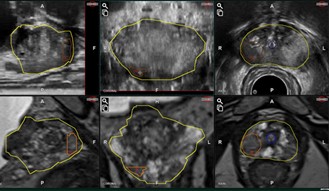

MRI-USフュージョン前立腺生検システムARIETTA 65 IntuitiveFusion

前立腺がんの診断精度向上と患者さんの負担軽減をめざし、MRI-USフュージョン前立腺生検システムARIETTA 65 IntuitiveFusionを導入致しました。